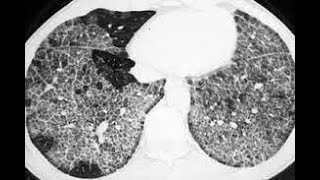

A Challenging Case of Influenza H1N1 Pneumonia and Pulmonary Alveolar Protienosis, Comprehensive